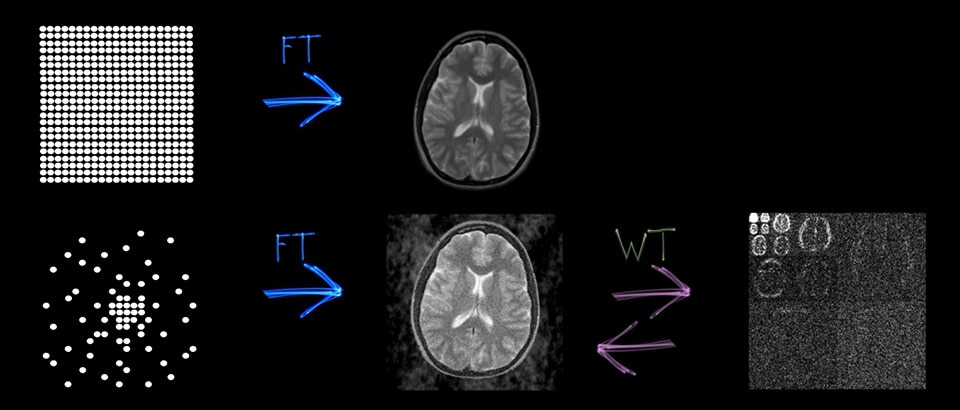

画像品質は実質的に同等1

空間分解能が最大64%向上1

画質は同等のまま高速化が可能1